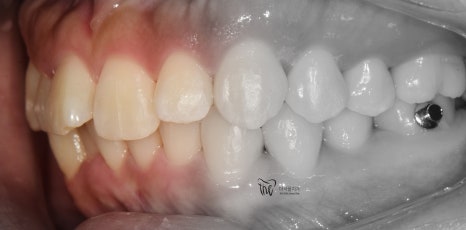

『23개월 소요, 최종 결과』

앞니의 기울기 변화에 따라서, 입술의 긴장감 또한

변화가 일어났습니다.

심미선을 기준으로, 입술의 위치가 그렇게

많이 변화가 된 것은 아니나 어찌되었건간에

심미선 안쪽에 입술이 위치 되는 것을 보실 수

있네요.

그러면서, 교정치료가 다 끝나가는 시점에서

임플란트를 심어서 맞물리는 대합치와의

기능 재건도 같이 진행했습니다.

정면에서 봤을 때, 앞니들 사이에 블랙트라이앵글이

조금씩 발생 된 부분은 살짝 아쉽긴 합니다.

그러나, 이는 과거 총생이 너무 심했기 때문에

어쩔 수 없이 발생이 될 수 밖에 없는 상황이였으며

이것을 제외하곤, 환자께서 얻으신 것이 많습니다.

가지런한 치열을 얻음에 따라서 구강 위생관리가

조금 더 용이해진 부분.

나아가, 부정교합 2급 이 같이 치료가 되면서

더불어 구강 내 충치들도 깔끔하게 다 제거를

해드리게 되었네요.

* 끝으로, 이 분은 처음에 오셨을 때

과개교합(Deep bite)의 양상을

가지고 있었습니다.

그러나, 최종 결과를 보면 과개교합이 많이

개선이 된 것도 같이 보실 수 있네요.^^